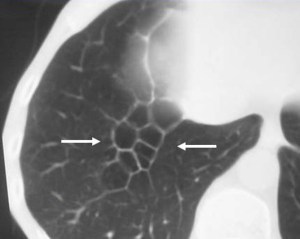

SIGNO DEL CASQUETE APICAL IZQUIERDO

La aparición de una densidad en el ápex pulmonar izquierdo, de borde inferior cóncavo y bien delimitado (casquete apical) en un paciente con traumatismo torácico, debe hacernos sospechar la existencia de una rotura aórtica.

Deben excluirse otras causas de casquete apical, especialmente las lesiones residuales tuberculosas, que suelen acompañarse de otros hallazgos como tractos fibrosos pleuro-parenquimatosos, pérdida de volumen en el lóbulo superior, granulomas, etc.

Mostramos un caso de rotura aórtica por accidente de moto. En este paciente también aparece el signo de la alteración del contorno aórtico.